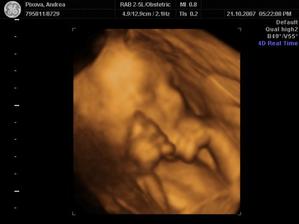

21.10.07 jsme byli i s tatínkem na 4D UTZ v Gennetu, vyšlo to moc pěkně, dokonce i pohlaví se jasně potvrdilo.